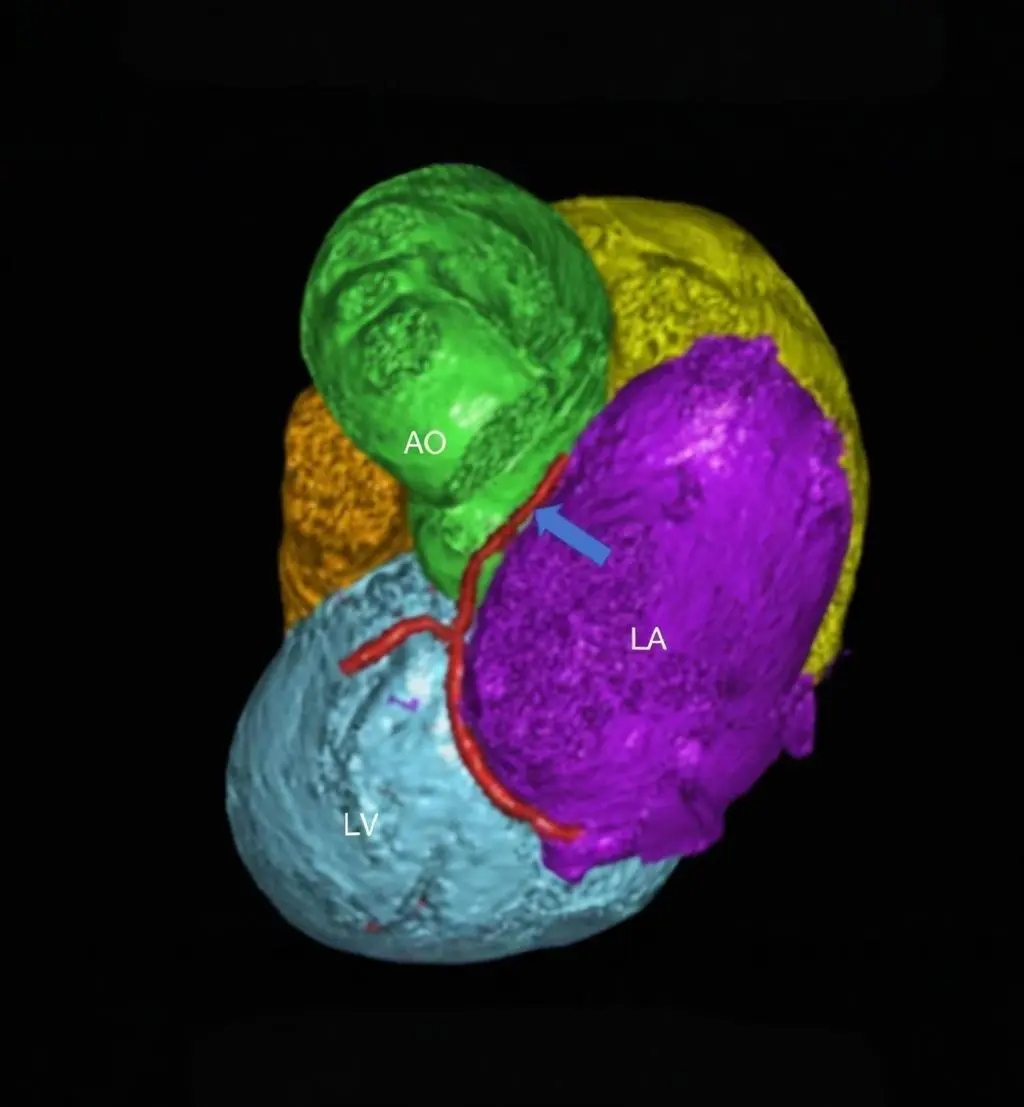

患者女性,27岁,因“卵圆孔未闭相关卒中”入院,拟行介入封堵术。术中MPA1导管跨越卵圆孔进入左心房后送入超滑导丝,发现导丝经由冠状静脉窦走行区回到右心房内,考虑导管进入异常通道,进一步造影可见一起自左心房前壁的冠状静脉分支血管沿房间隔水平横行走行,造影剂最终汇入冠状静脉窦,引流入右心房(图1&2,视频1&2)。该病情血液动力学类似冠状静脉无顶综合征/房间隔缺损,同期行右心导管测肺动脉平均压16mmHg,QP/QS=1.0,排除具有血液动力学意义的左向右分流。由于无法立刻明确单纯封堵PFO的收益与风险,遂终止手术先行完成心脏增强CT明确病变解剖情况,增强CT(图3&4)及重建结果(图5&6)与造影一致,可见一冠状静脉分支起自左心房并沿房间隔走行最终汇入冠状静脉窦。考虑到患者的临床症状可能与PFO以及该异常静脉均存在相关性,且尚不能明确单纯封堵PFO的收益以及同期封堵该静脉的风险,与患者充分沟通后暂时选择最优药物治疗并保持密切随访。

图6